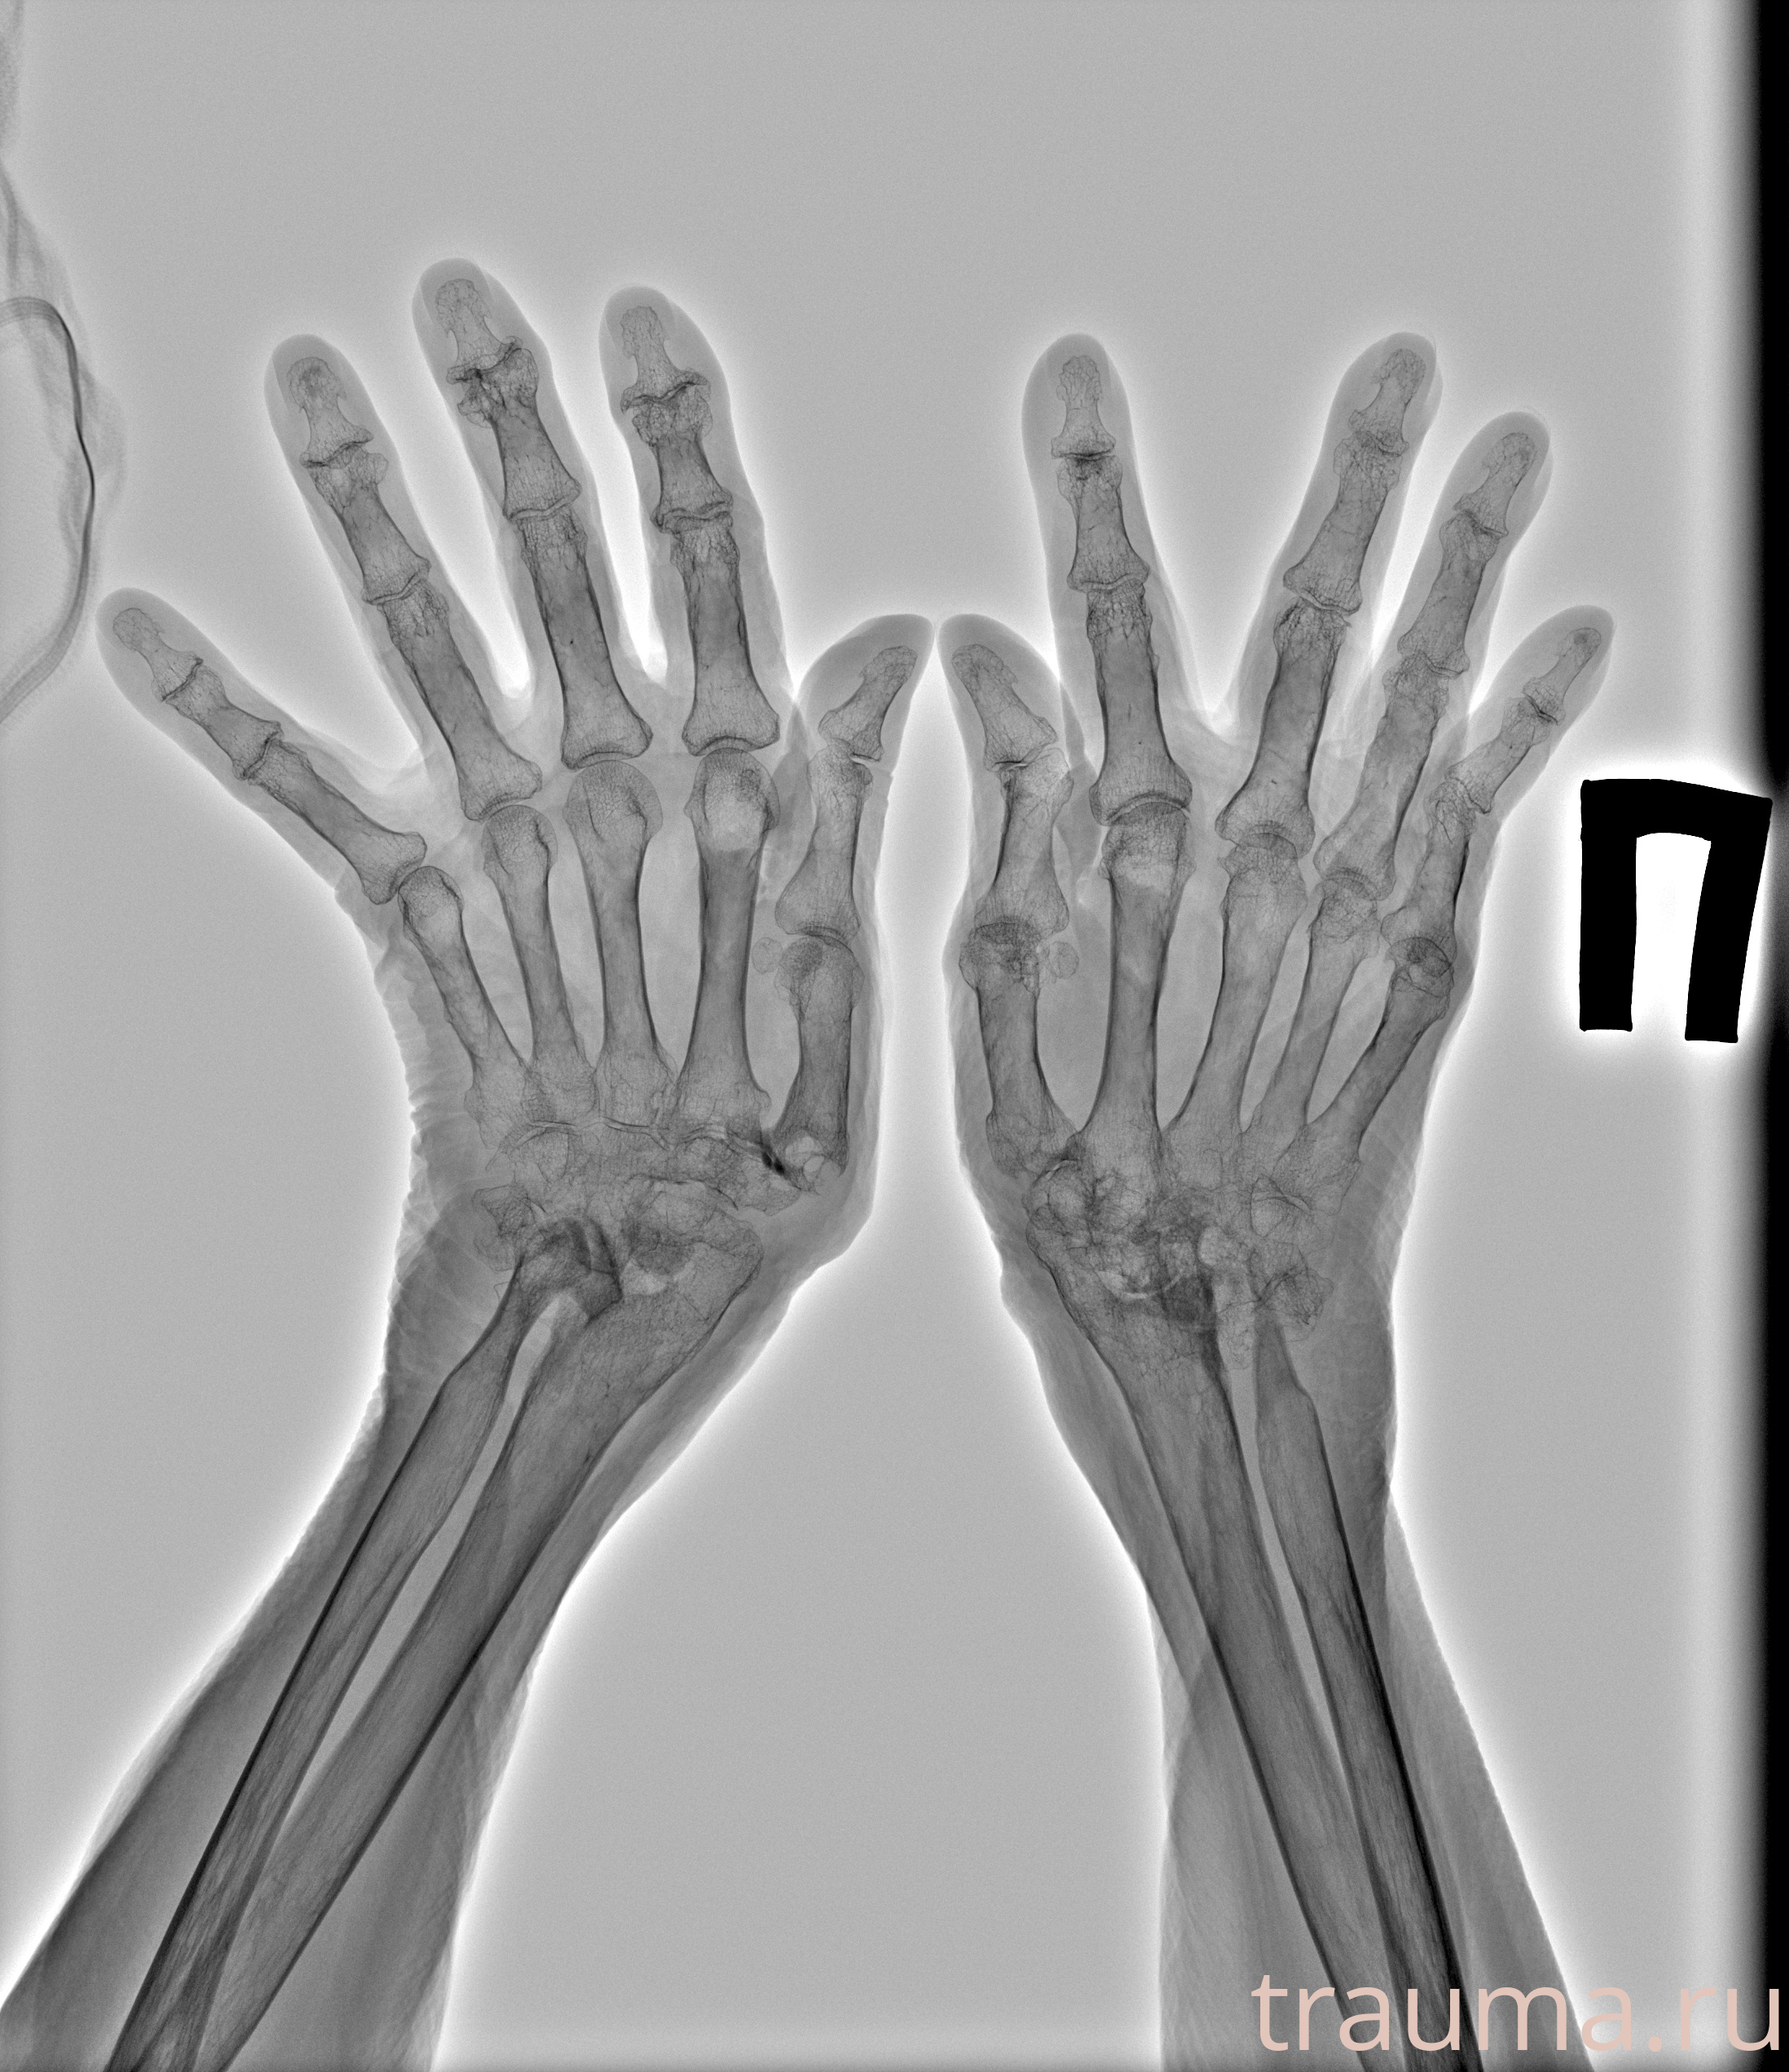

Рентген на дому: по вашему адресу приезжает врач-рентгенолог, травматолог-ортопед с мобильным рентгеновским аппаратом, проводит диагностику травмы или заболевания, делает необходимые рентгенограммы, дает рекомендации по дальнейшему лечению. Получить качественные снимки в домашних условиях возможно благодаря уникальной методике, разработанной МосРентген Центром для института  Склифосовского